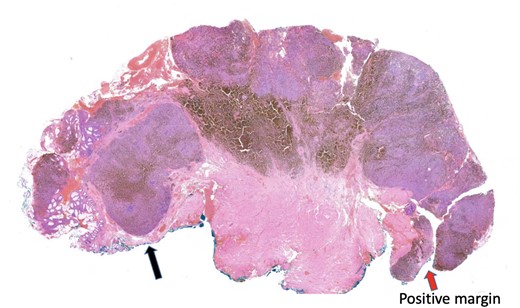

The histopathology report found an ulcerated AMM with positive SOX10, MelanA, and HMB45 immunohistochemistry. The lesion had a mitosis count of 12 per mm2, lymphovascular invasion, no tumour necrosis and BRAF negative. The tumour invaded to a depth of 8 mm into the submucosa, with involved peripheral margins and a deep margin clearance of 1 mm (Fig. 1).

Histopathology slide with involved peripheral margin, labelled ‘Positive margin’.